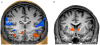

Many patients show no or incomplete responses to current pharmacological or psychological therapies for depression. Here we explored the feasibility of a new brain self-regulation technique that integrates psychological and neurobiological approaches through neurofeedback with functional magnetic resonance imaging (fMRI). In a proof-of-concept study, eight patients with depression learned to upregulate brain areas involved in the generation of positive emotions (such as the ventrolateral prefrontal cortex (VLPFC) and insula) during four neurofeedback sessions. Their clinical symptoms, as assessed with the 17-item Hamilton Rating Scale for Depression (HDRS), improved significantly. A control group that underwent a training procedure with the same cognitive strategies but without neurofeedback did not improve clinically. Randomised blinded clinical trials are now needed to exclude possible placebo effects and to determine whether fMRI-based neurofeedback might become a useful adjunct to current therapies for depression.